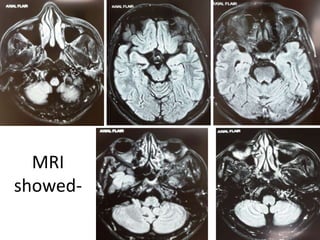

• 65 year old female presented to the hospital

with sudden onset of vertigo.

• Associated with headache, vomiting, swaying

of gait, blurred vision, diplopia.

• K/C/O Hypertension.

• O/E- Deviation of mouth.

– Cerebellar signs present.

– Left plantar extensor.

CT showed